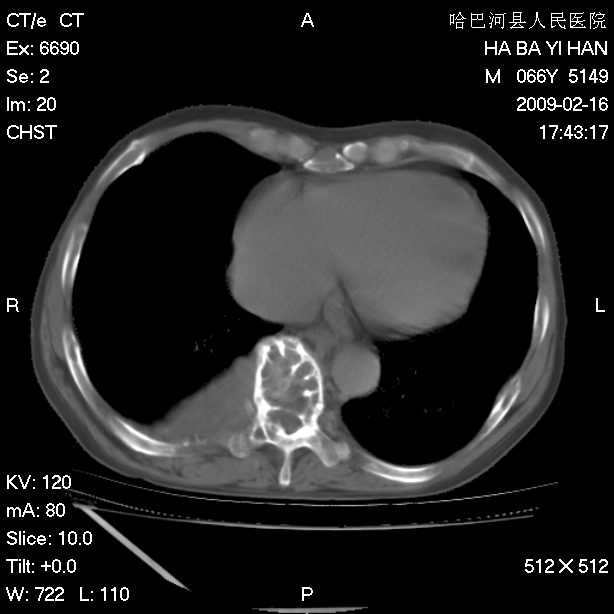

以下是引用huangxun4321在2009-2-16 20:18:00的发言:[br]部分病灶可见硬化边,部分可见骨质破坏消失,部分病灶内可见骨脊,说明病灶内既有良性病变,又有恶性病变,考虑骨巨细胞瘤恶变,未除骨纤恶变,畸形性骨炎少见,亦要考虑.

以下是引用731208在2009-2-16 20:31:00的发言:[br]考虑恶性胸膜间皮瘤并肋骨,脊柱转移。

以下是引用yijiansheng在2009-2-16 20:16:00的发言:[br]考虑恶性胸膜间皮瘤并肋骨,脊柱转移。

以下是引用形影不离在2009-2-16 19:55:00的发言:[br]考虑多发性转移瘤。